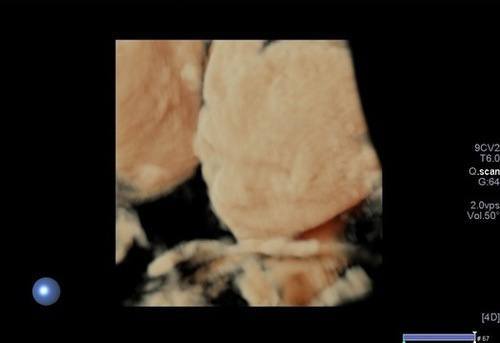

3/4 boyutlu ya da renkli ultrason olarak adlandırılan inceleme ise bebeğin yüzü ya da vücudunun bir kısmının (kollar, bacaklar, eller,ayaklar gibi ) görüntülenmesi anlamına gelir. Bu incelemenin tanısal bir katkısı olmamakta olup daha çok anne, baba ve yakınları için hatıra için yapılmaktadır.